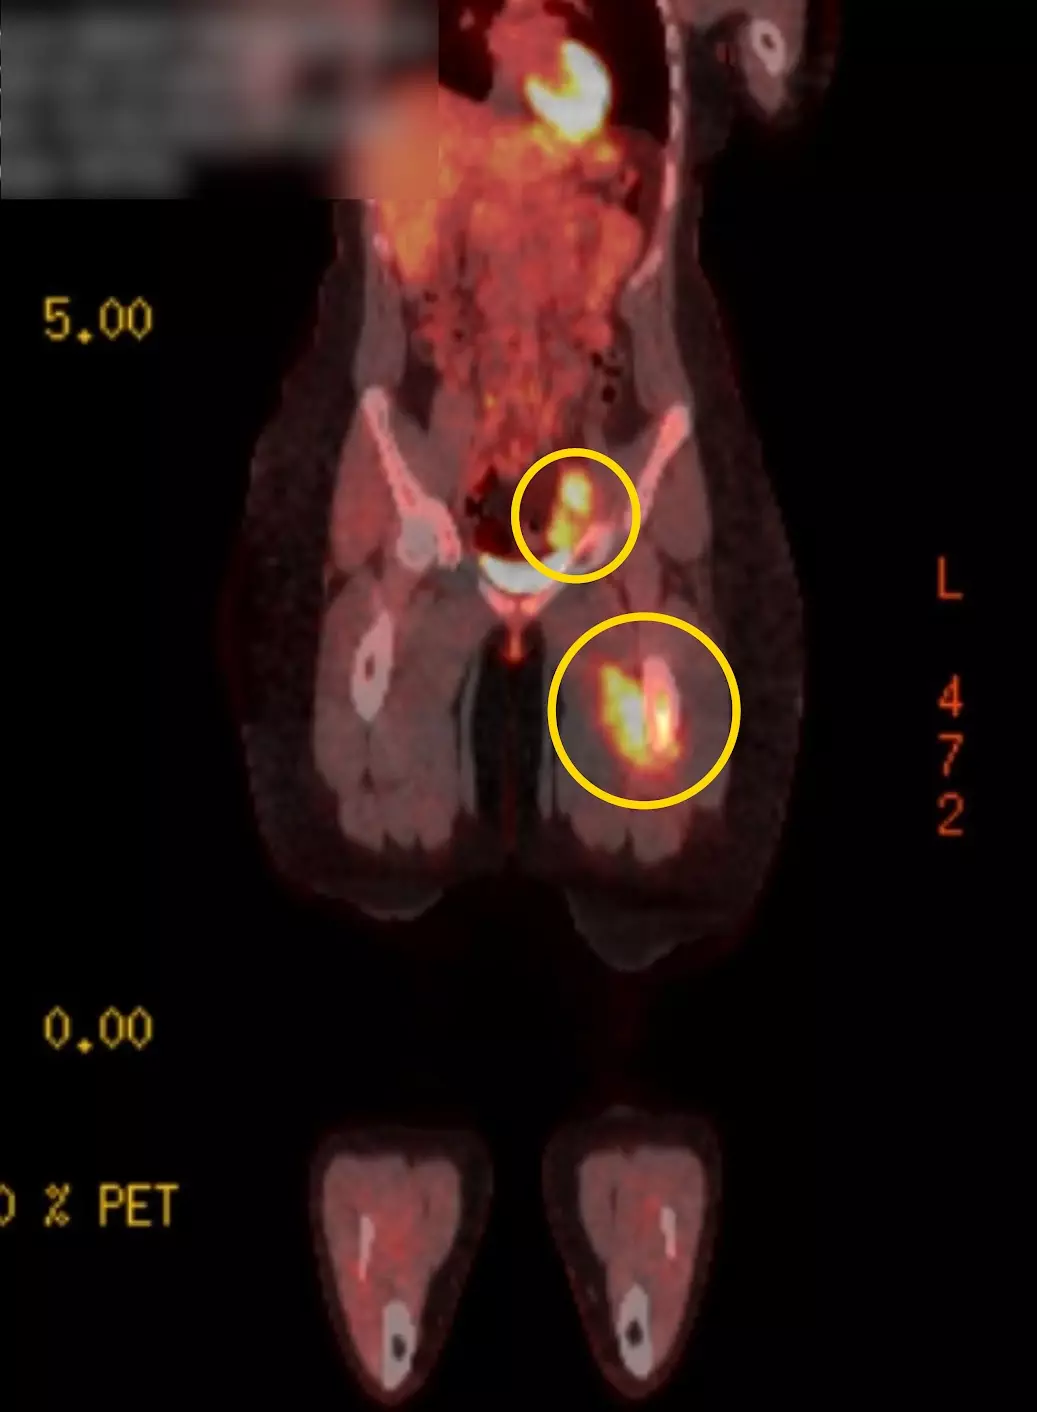

Results from the scan revealed Bailey had two tumors, one located in her femur and another in her groin, and she was diagnosed with stage four Ewing sarcoma, a form of soft tissue cancer.